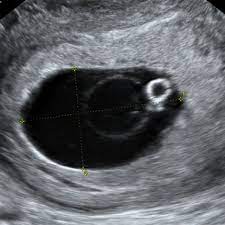

El ultrasonido del primer trimestre es el método más preciso para establecer o reafirmar la edad gestacional.

Para mayor exactitud en el cálculo de la duración del embarazo, las edades gestacionales calculadas a partir del último periodo menstrual se comparan con la ecografía del primer trimestre.